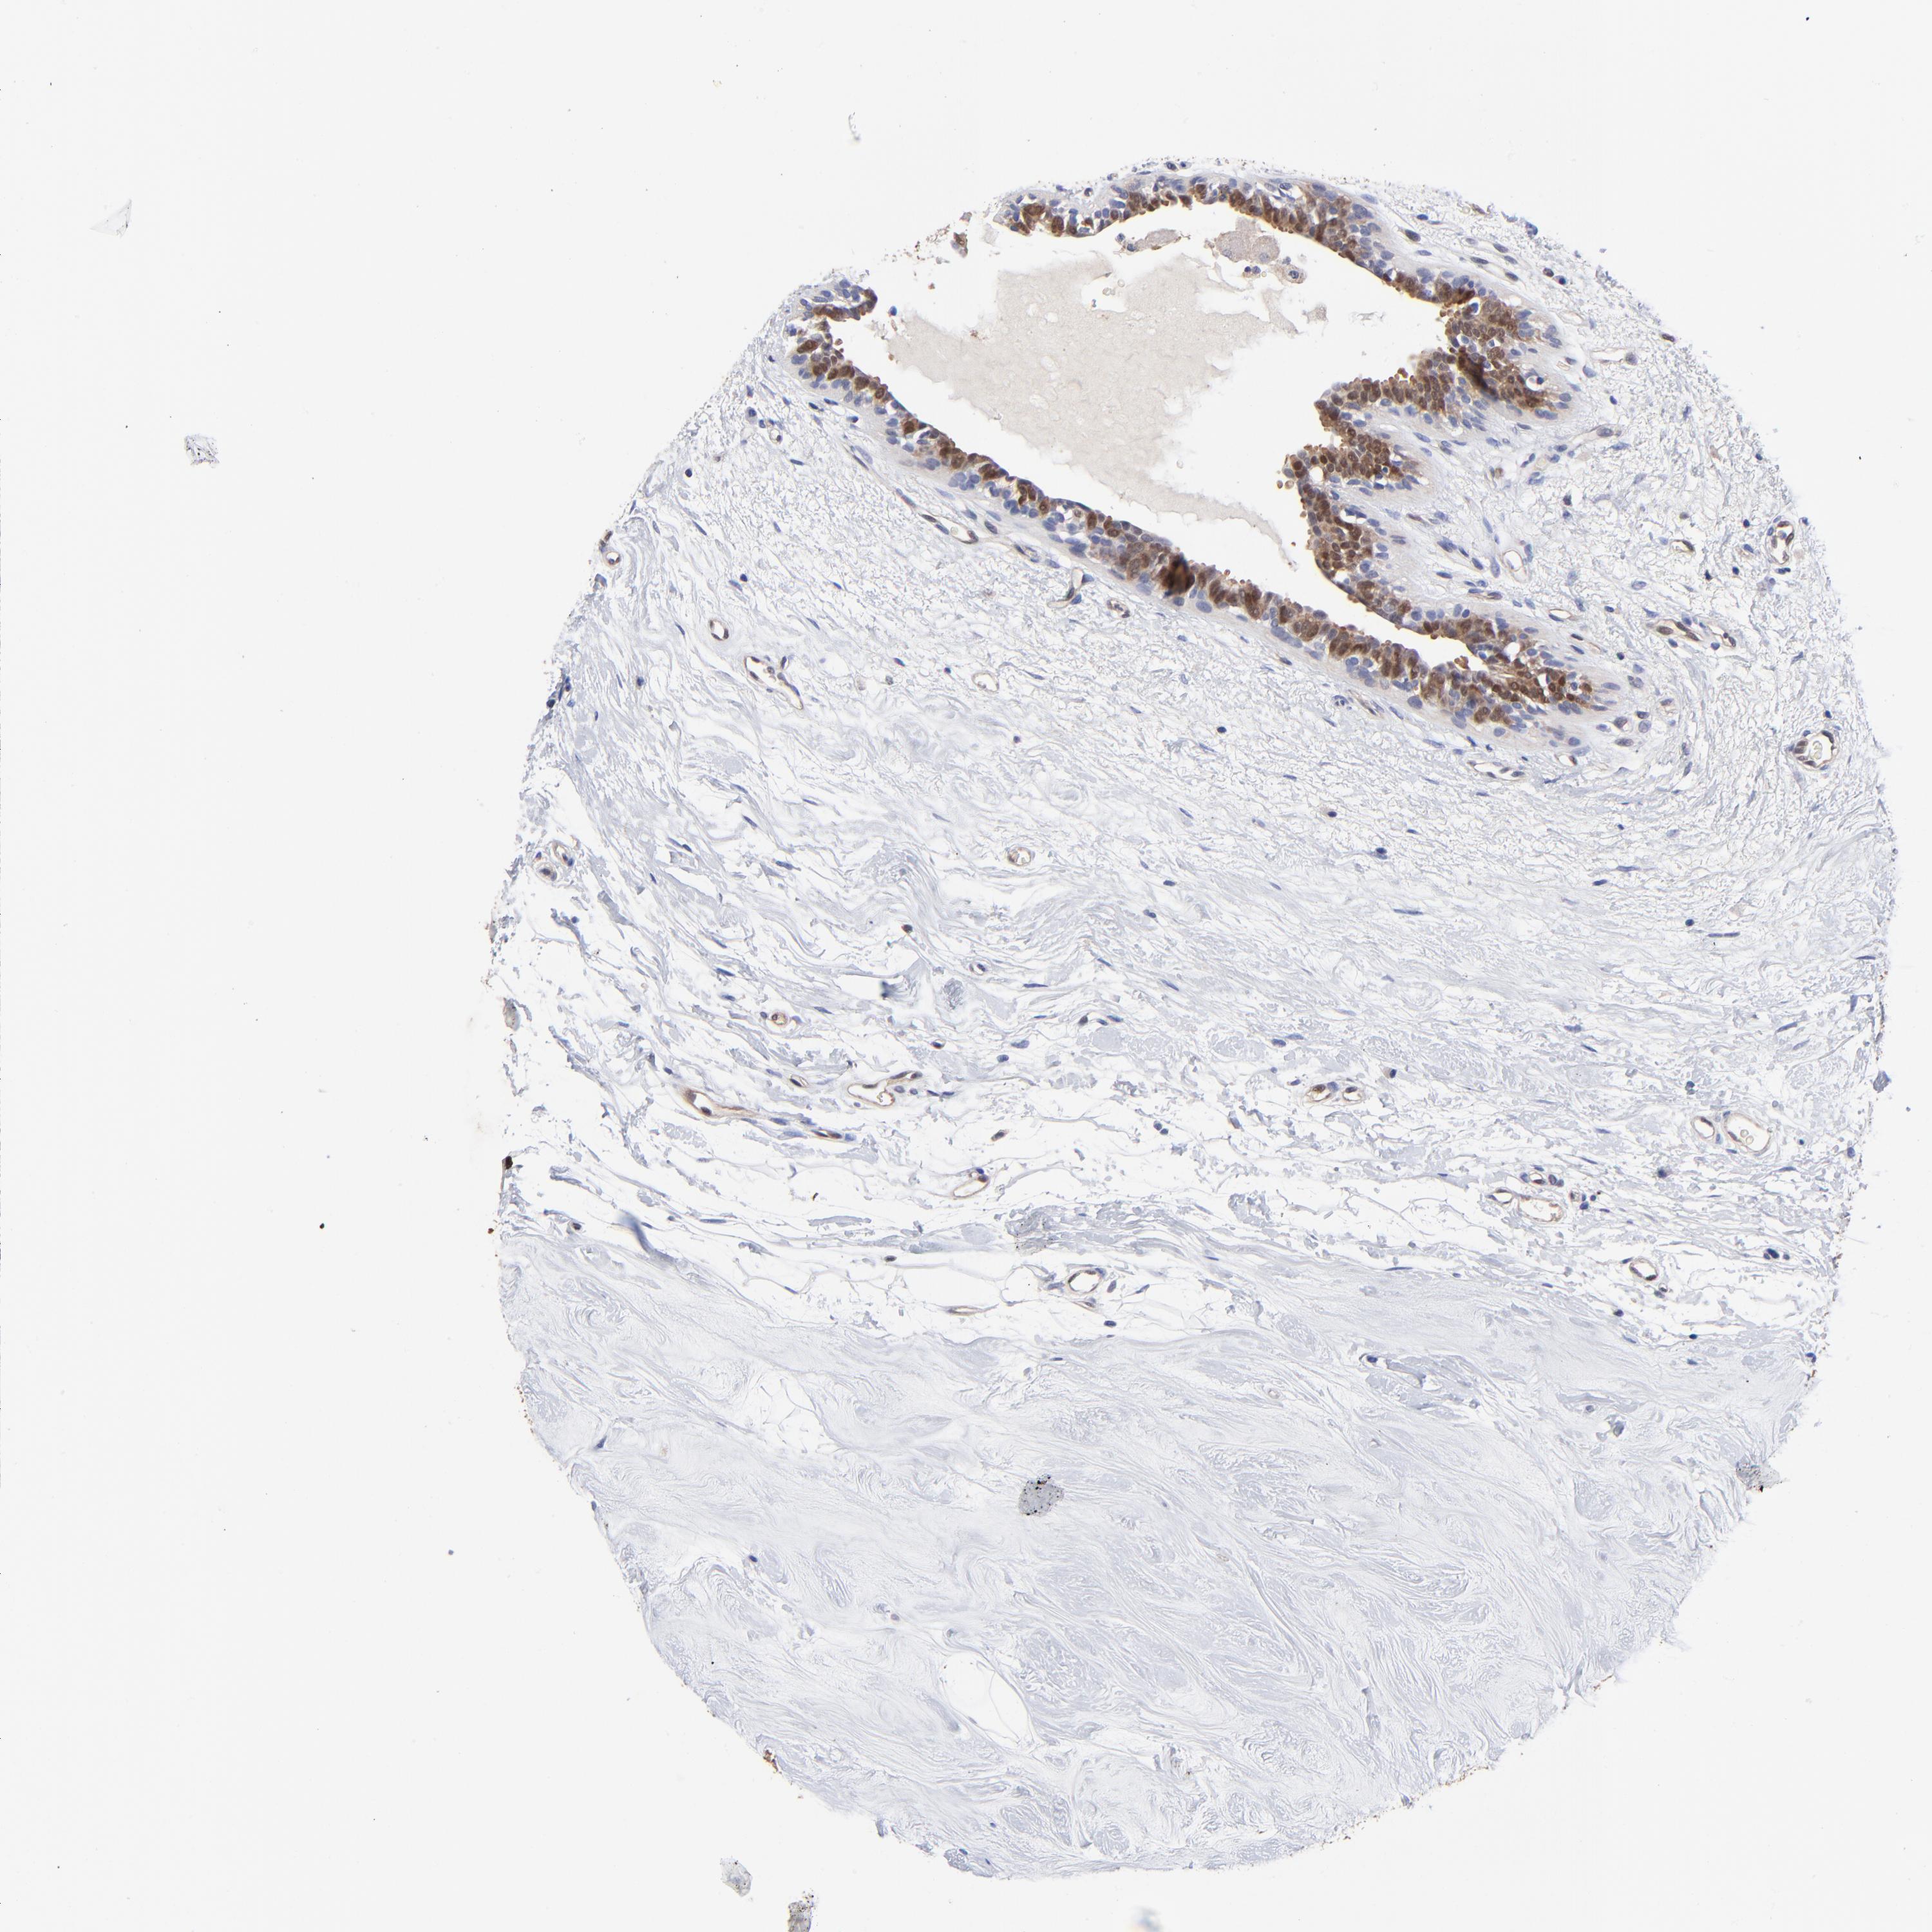

BRCA TCGA BRCA VALIDATION PROTEIN EXPRESSION

ANTIBODIES

AND

VALIDATION